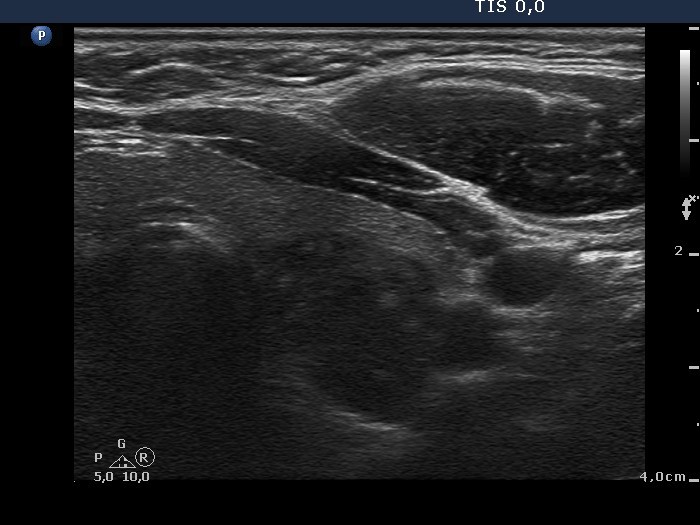

Chronic lymphocytic thyroiditis - Case 45. (ultrasonographic picture 3)

Left lobe, horizontal scan. There is a large hyperechogenic lesion with irregular borders in the dorsal part of the thyroid.